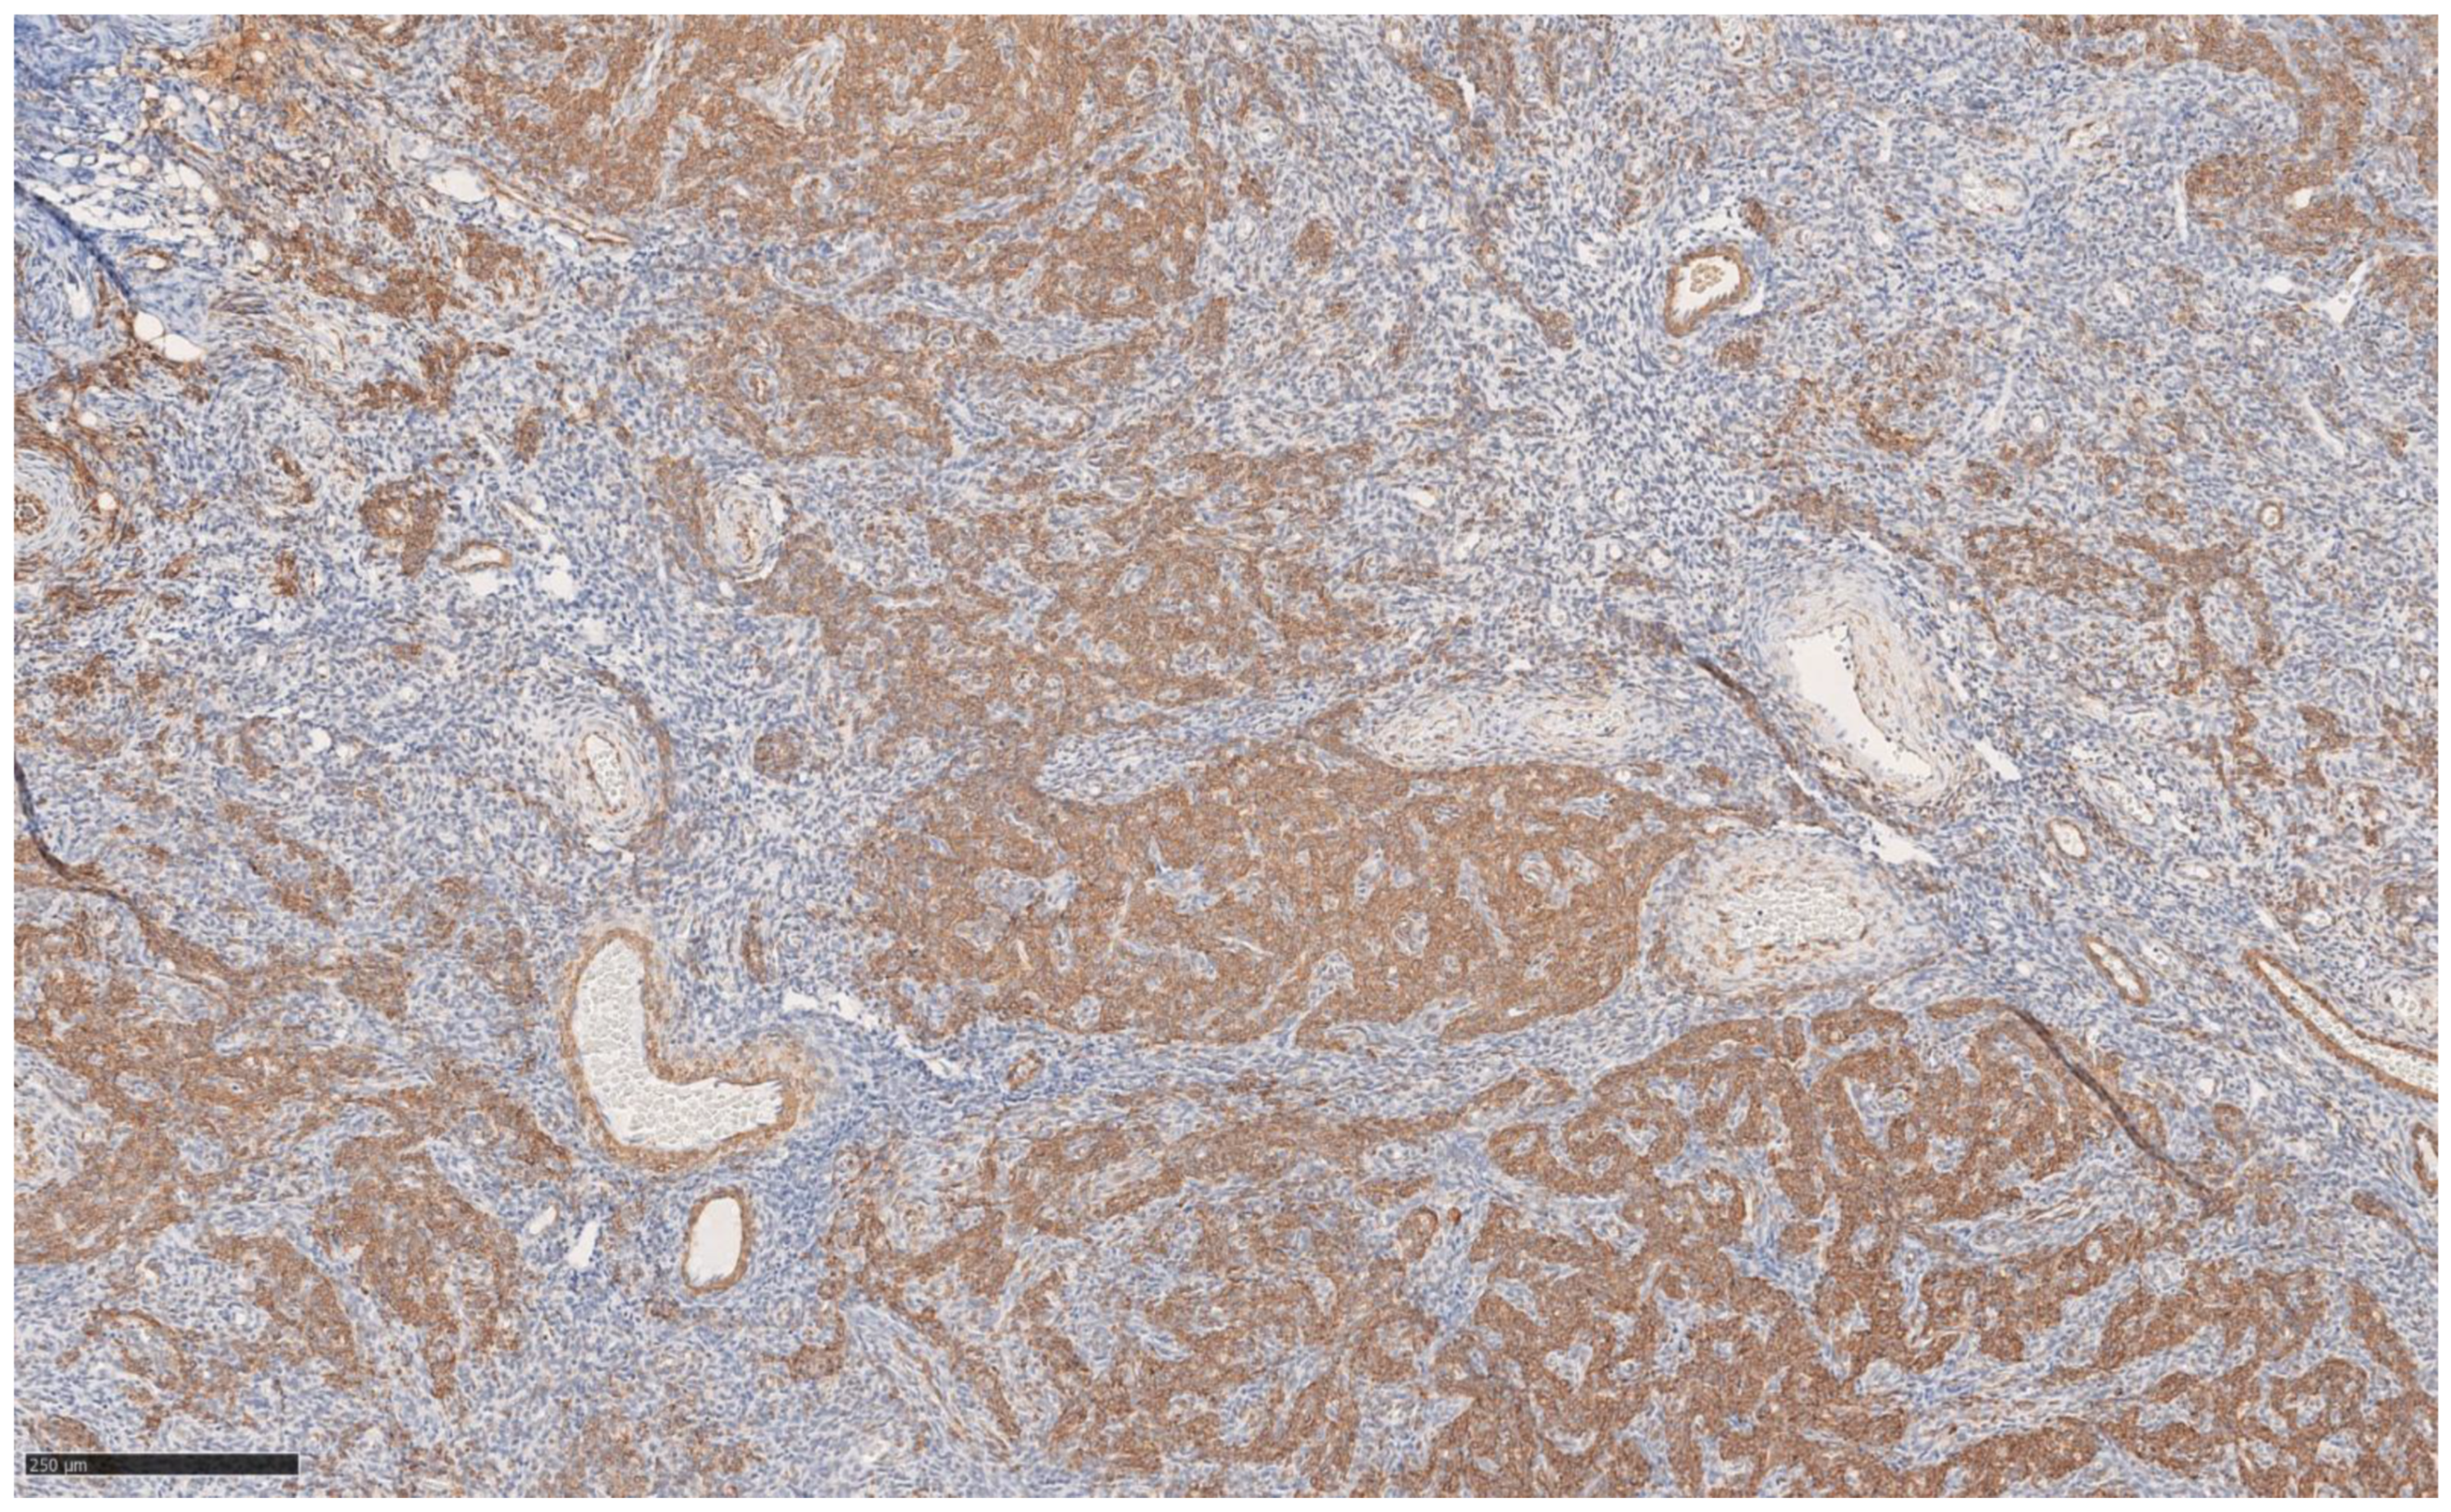

4.3. Histological and Immunohistochemical Features